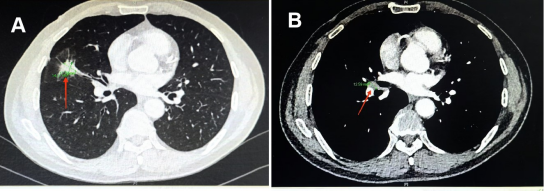

经过4个周期的治疗,向先生的肺部病灶显著缩小,肺门淋巴结也明显缩小(见图3),整个治疗过程中也没有发生明显的不良反应。经过医院MDT(多学科团队协作)会诊,向先生的小细胞肺癌分期成功由IIIA期降至IIA期,大家一致认为已达到手术条件和要求。8月23日新桥医院胸外科在全麻下为向先生做了肺癌根治性切除手术。手术过程顺利,术后的病理结果显示切除的病灶和淋巴结中没有发现肺癌细胞,达到了病理完全缓解(PCR)(见图4)。向先生术后恢复良好,精神状态和气色俱佳,5天后高兴地出院回家。

图3 经过4周期治疗后肺部原发病灶明显缩小(见图A红色箭头)和肺门淋巴结明显缩小(见图B红色箭头)